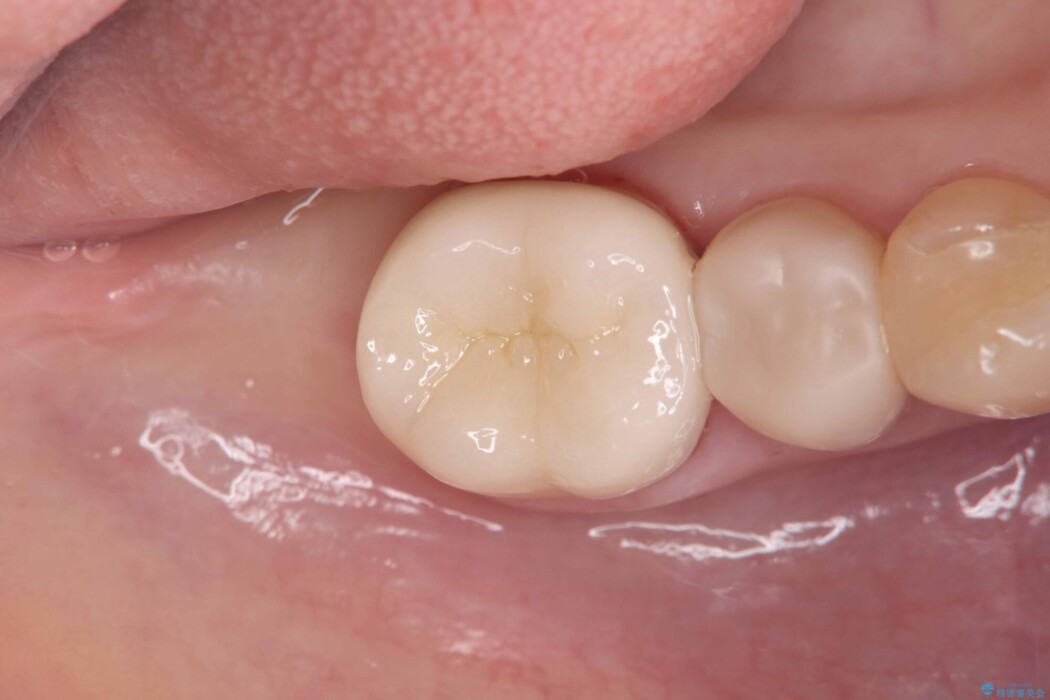

破折の再発防止および歯質保護を最優先に考え、オールセラミッククラウンによる治療を計画しました。

このようなケースでは、部分的に詰める治療よりも歯全体を覆うクラウンの方が強度的に有利です。

そのため今回は、歯をしっかり保護し、長期的な安定を図るために、オールセラミッククラウンによる修復を行いました。

クラウンにすることで、噛む力を分散しながら歯を保護できるため、再び割れてしまうリスクを大きく下げることが可能です。